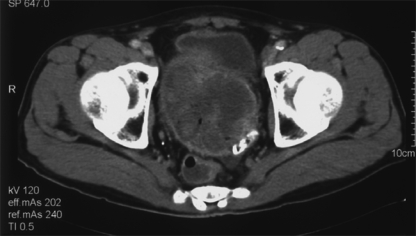

image = Image.open("ROCO_04197.jpg")

An example response.

Computed tomography scan showing a large heterogenous mass in the pelvis<|eot_id|>